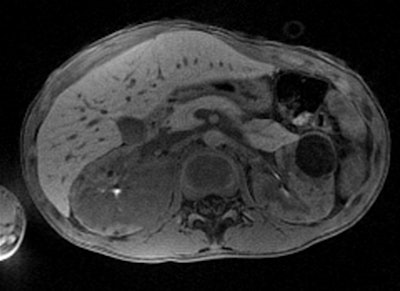

StarVIBE is a new pulse sequence that enables free-breathing, contrast-enhanced liver imaging for patients who are unable to easily manage breath-holding, such as those who are old, very ill, or young. Meanwhile, TWIST-VIBE is intended for more accurate contrast imaging in dynamic liver MRI scans for all patients and lesions, allowing faster liver imaging with full 4D coverage.

With Siemens' StarVIBE technology, no breath-hold is needed. The images above and below show the increase in image quality with StarVIBE. Images courtesy of Siemens.